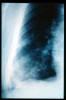

Neumonía abscesificada.